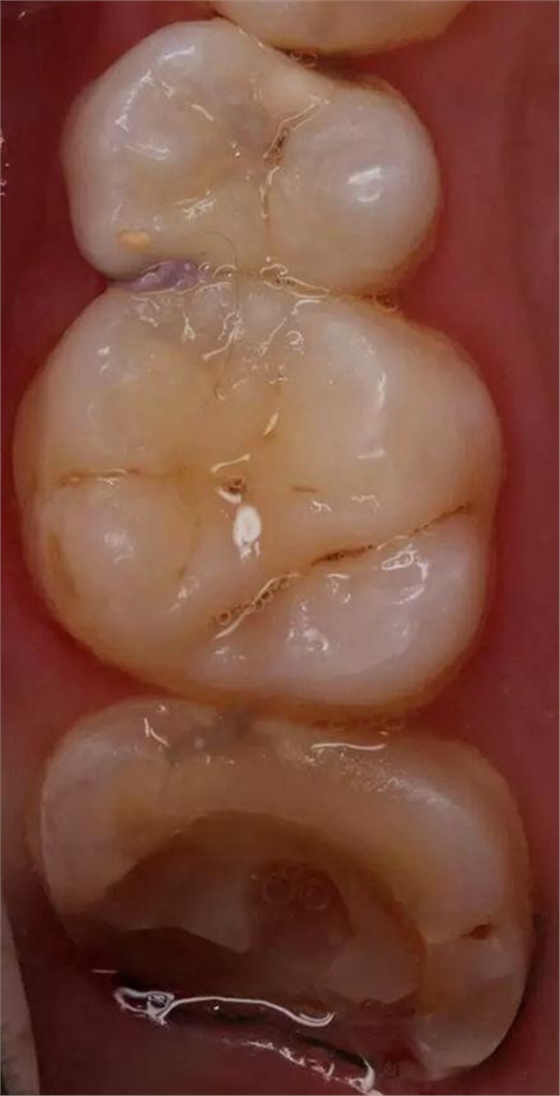

排齦后樹(shù)脂充填,高嵌體制備

取模后用樹(shù)脂自行高嵌體制作,咬合通過(guò)對(duì)合調(diào)整,領(lǐng)面用彈性樹(shù)脂去除法調(diào)整,有些照片未拍攝